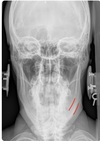

NASIUM ANATOMICAL LANDMARKS

upper teeth

54

medial inferior tip of condyle

55

Nasium view

nasal septum + spine

56

transverse process of c1-c3

57

lower teeth

58

spinous process c2-t1

59

nasal aperture

60

maxillary sinus

61

frontal sinus

62

mastoid (air cells) process

63

lateral mass c1

64

occipital-atlantal joint space

65

atlantal-axial joint space

66

mandible body

67

mandible ramus

68

mandible angle

69

mandible mentum

70

odontoid process

71

articular pillar